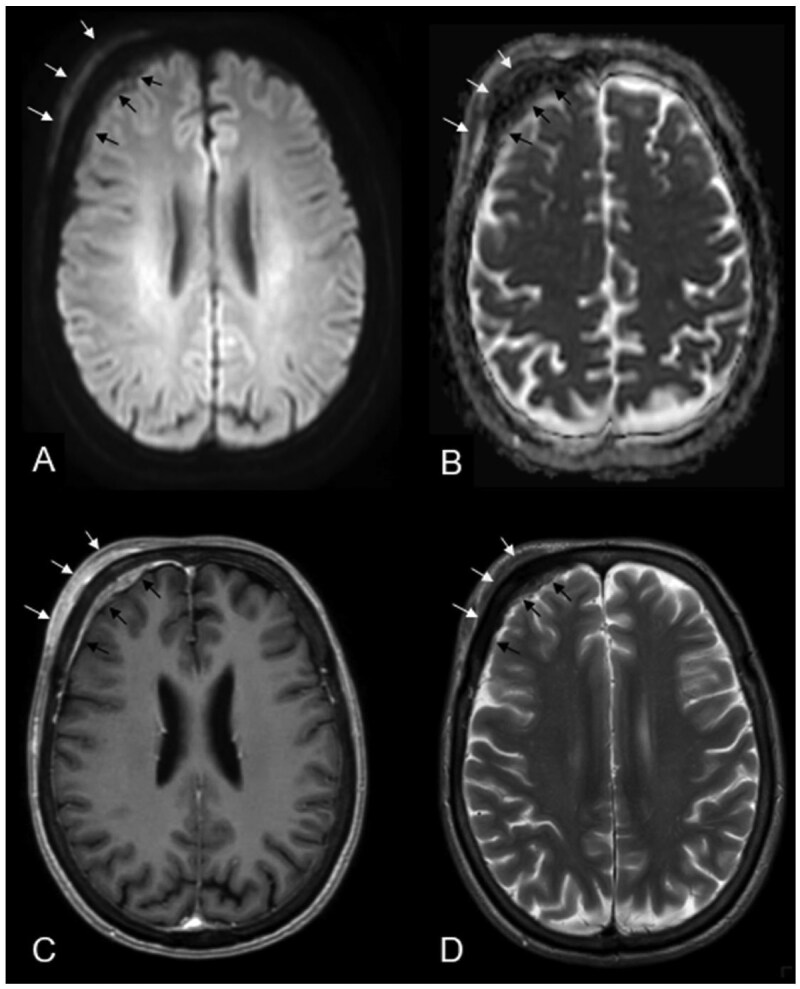

Primary central nervous system (CNS) mucosa-associated lymphoid tissue (MALT) lymphoma is a rare condition frequently mistaken for meningioma. Since these conditions require distinct treatment approaches, recognizing their imaging characteristics is essential for accurate clinical decision-making. A 69-year-old woman presented with headaches and forehead swelling, prompting MRI of the CNS. Suspecting an intracranial meningioma, the tumour board recommended surgical resection. However, histopathological analysis identified the lesion as a primary CNS MALT lymphoma. Follow-up revealed secondary cutaneous tumour infiltration, leading to a delay in adjuvant radiotherapy. Understanding the differential diagnoses of meningioma is critical for neuroradiologists and neurosurgeons to ensure appropriate treatment planning. This case highlights a misdiagnosis of meningioma that was ultimately identified as a primary CNS MALT lymphoma, emphasizing key imaging and clinical characteristics essential for distinguishing between the most important differential diagnoses of primary CNS MALT lymphoma.